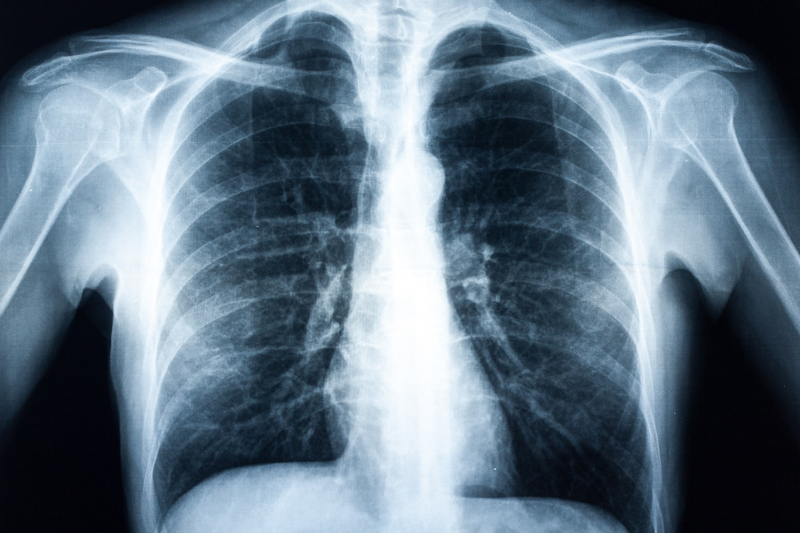

As part of one of Australia's leading health services, Alfred Health Radiology is one of the most advanced radiology departments in the country. We are accredited to DIAS (Diagnostic Imaging Accreditation Scheme) in all modalities excluding DEXA and research.